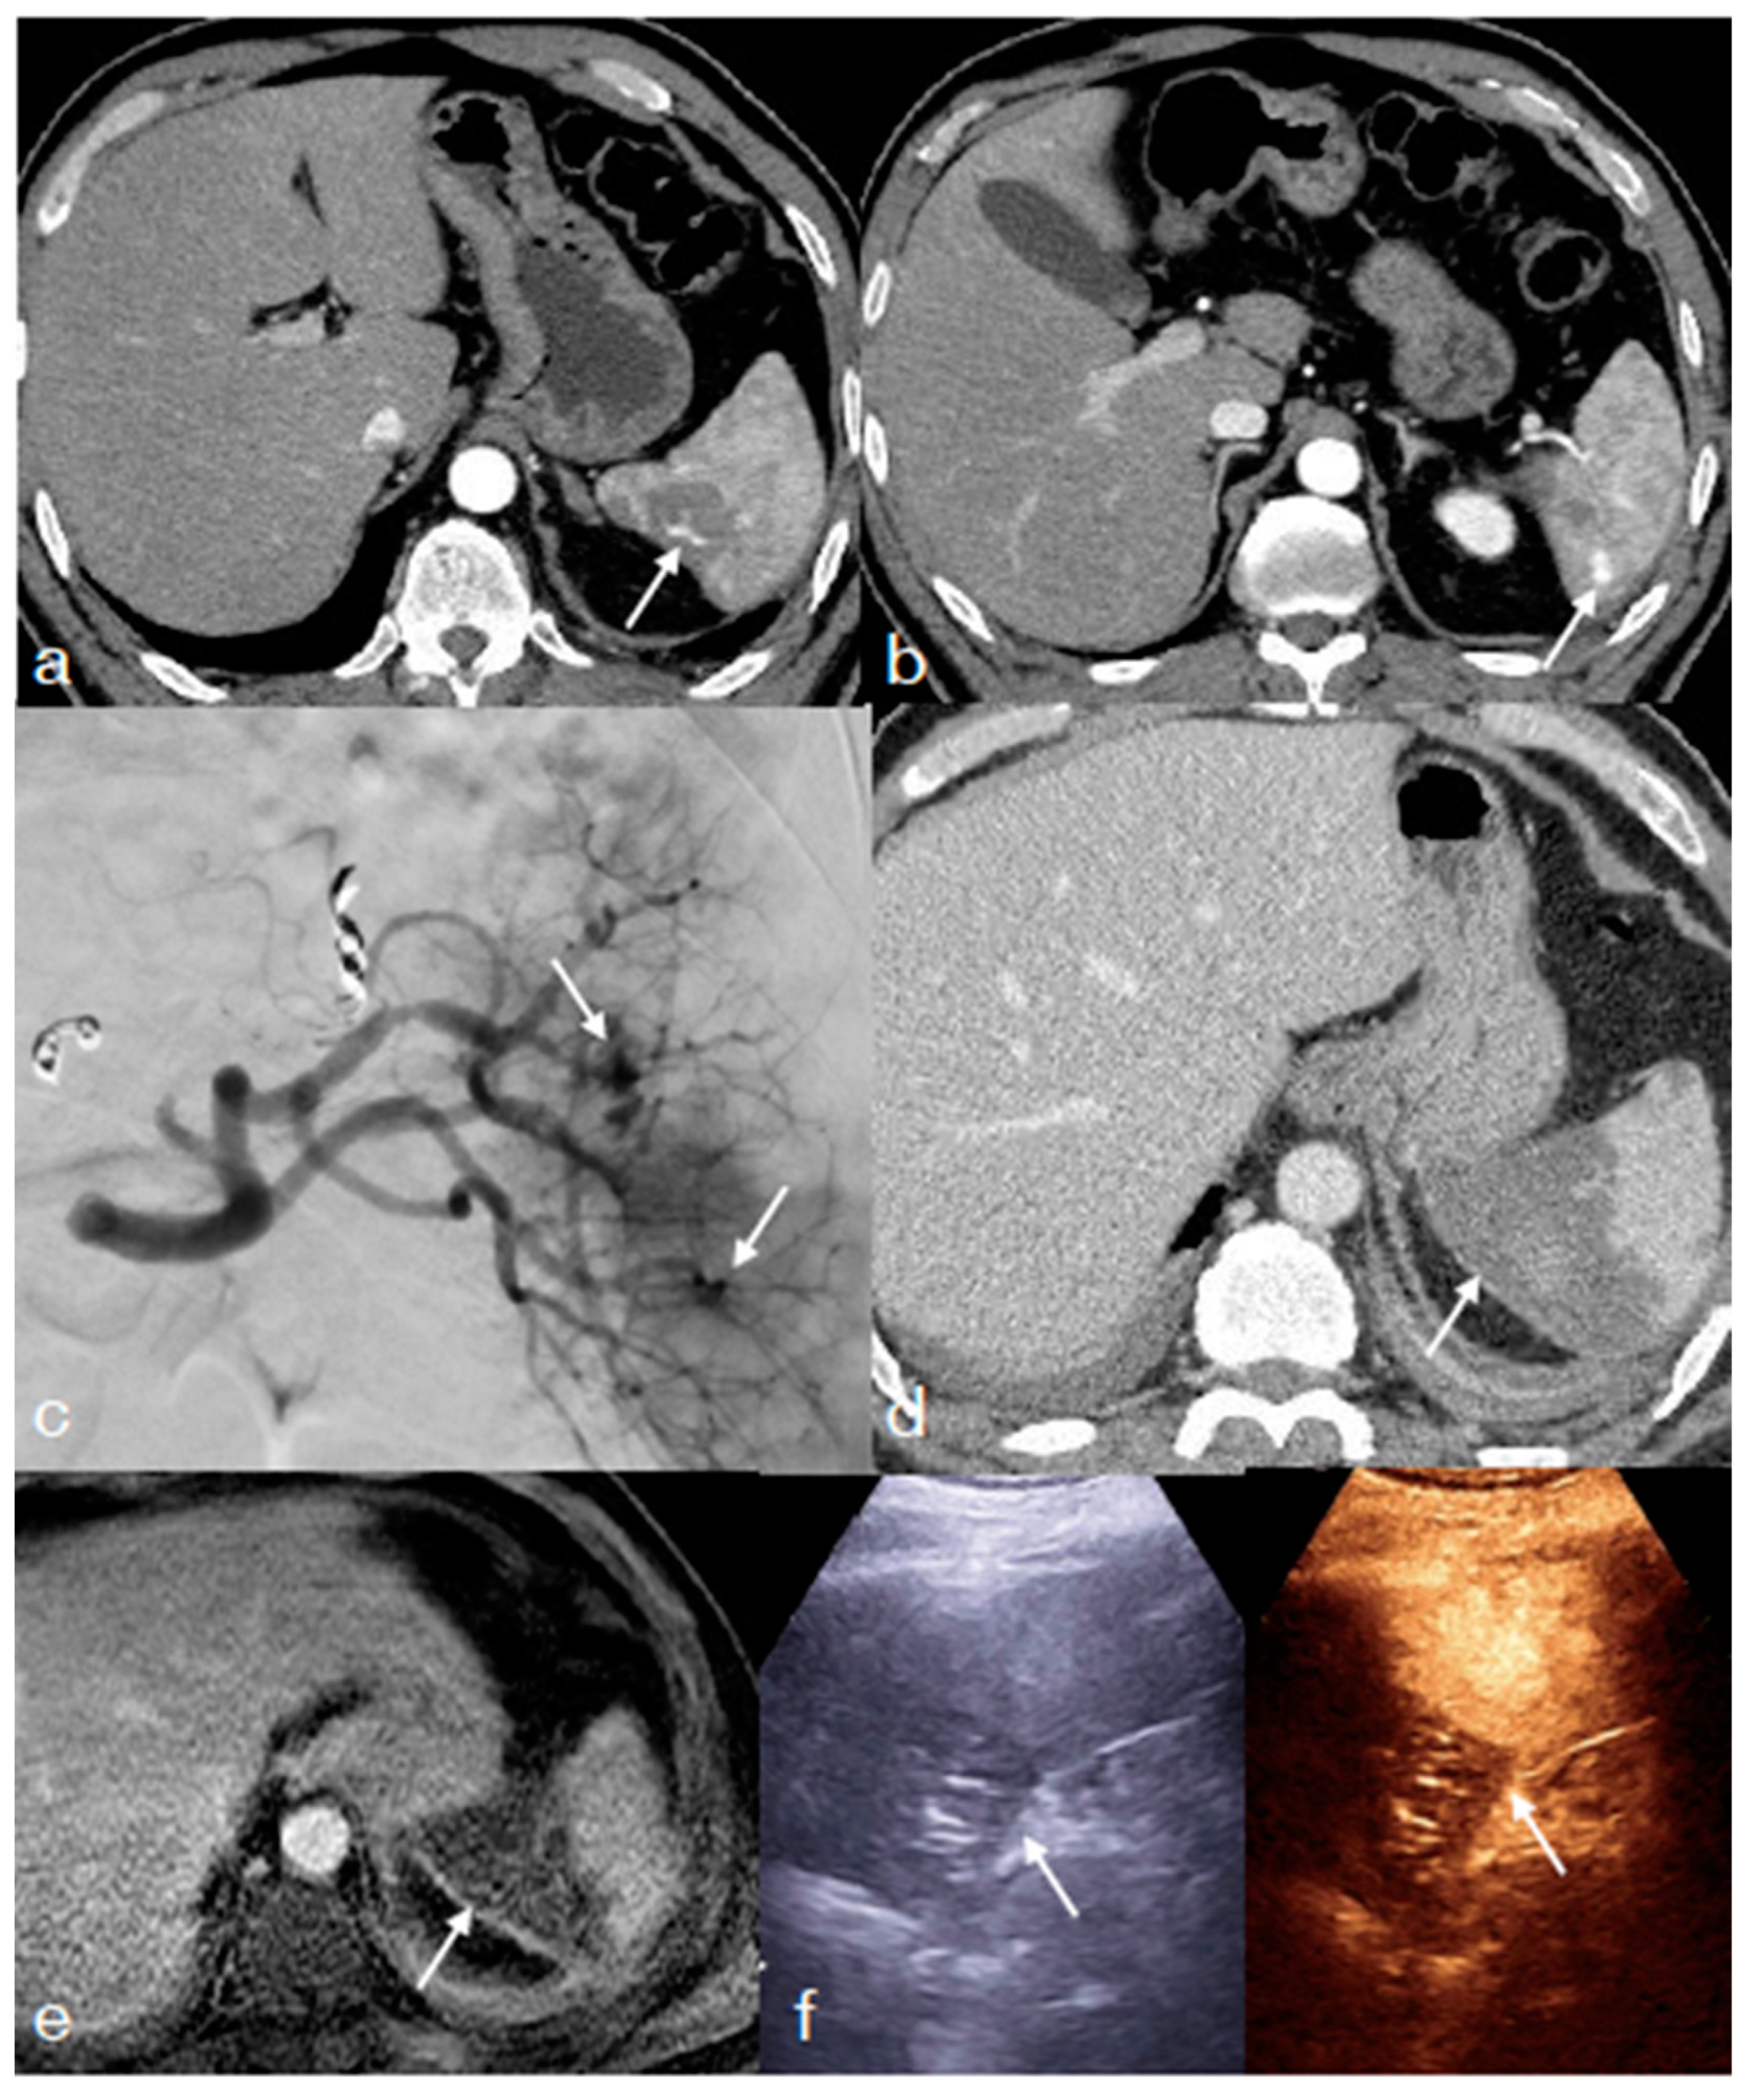

- Iacobellis, F.; Di Serafino, M.; Brillantino, A.; Mottola, A.; Del Giudice, S.; Stavolo, C.; Festa, P.; Patlas, M.N.; Scaglione, M.; Romano, L. Role of MRI in early follow-up of patients with solid organ injuries: How and why we do it? Radiol. Med. 2021, 126, 1328–1334. [Google Scholar] [CrossRef] [PubMed]

- Miele, V.; Piccolo, C.L.; Sessa, B.; Trinci, M.; Galluzzo, M. Comparison between MRI and CEUS in the follow-up of patients with blunt abdominal trauma managed conservatively. Radiol. Med. 2015, 121, 27–37. [Google Scholar] [CrossRef] [PubMed]